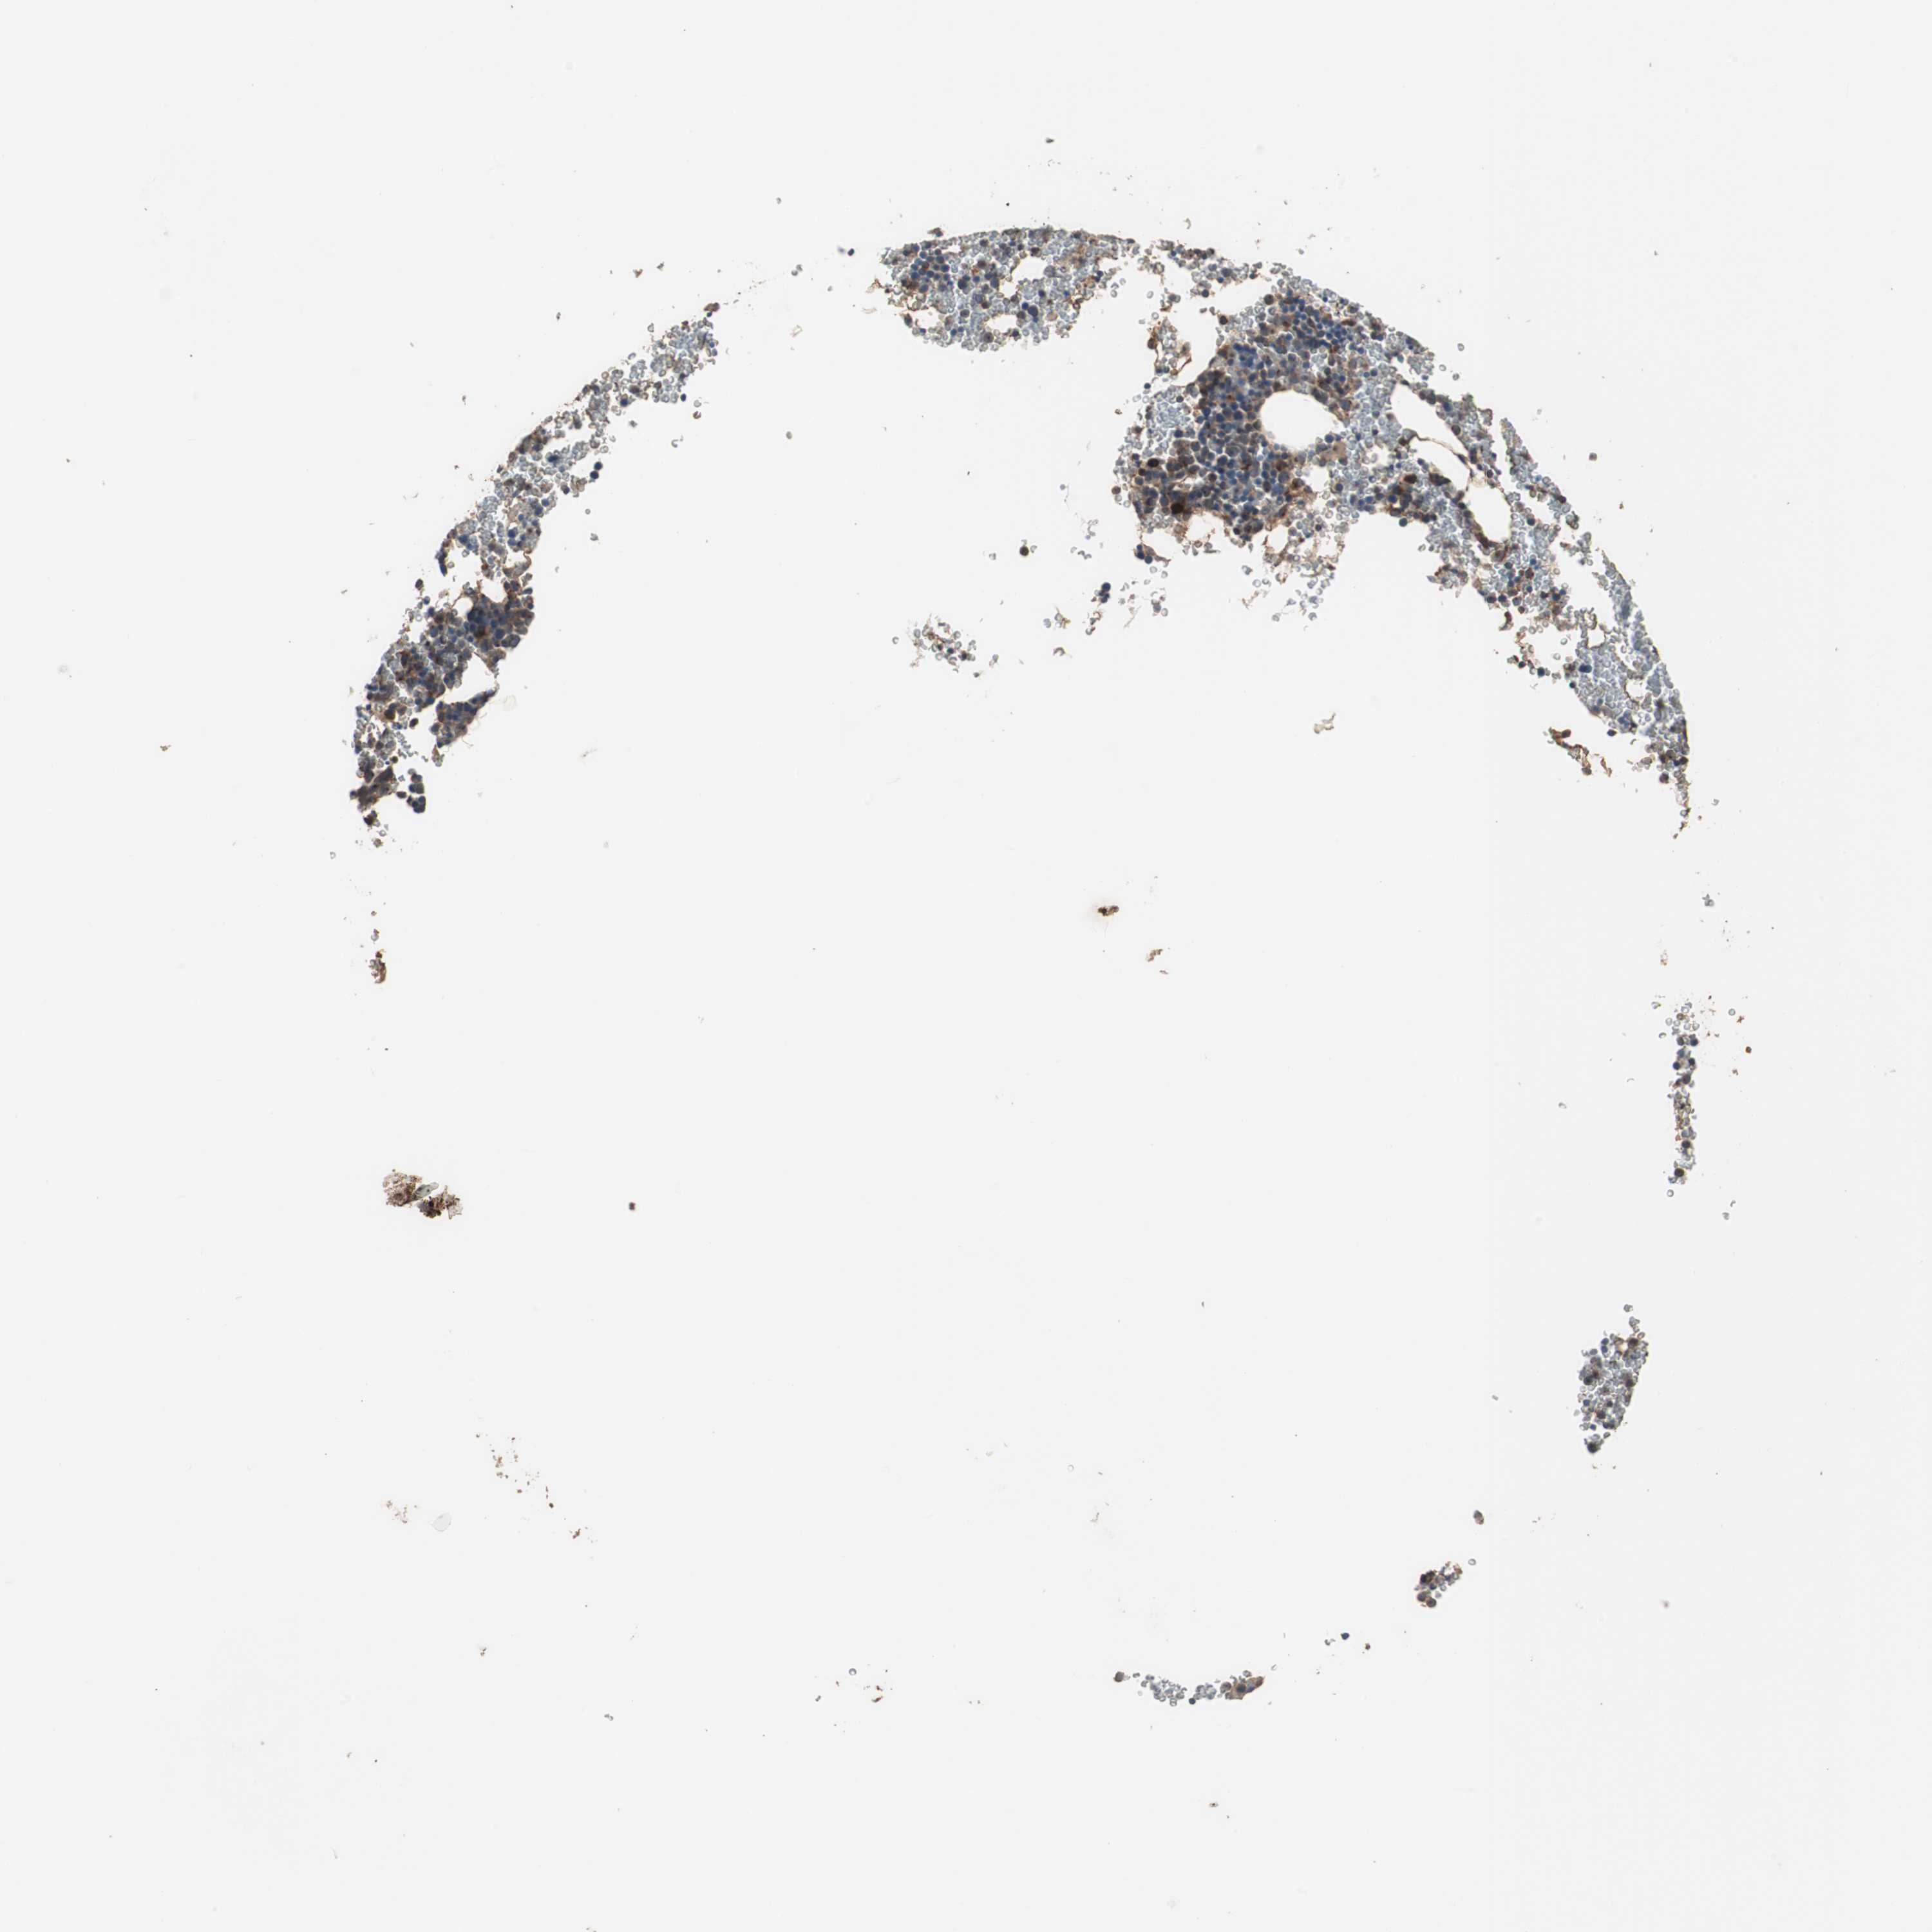

LZTS1